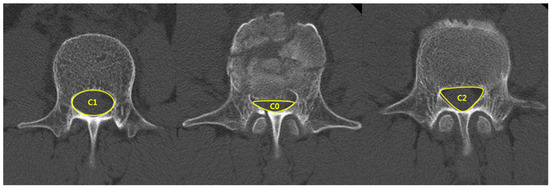

| Spinal canal compromise (%) ‡ | 27.9 ± 7.6 | 35.7 ± 13.3 | 0.03 |